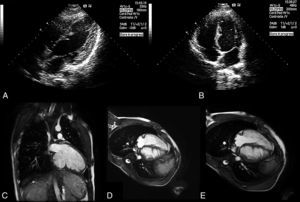

Aos 16 anos, o ecocardiograma mostrava numerosas projeções miocárdicas ecodensas com morfologia em «dentes de serra» na parede inferior, lateral e septo posterior do ventrículo esquerdo (VE), com protusão para a sua cavidade (painéis A e B).

Painel A – ecocardiograma transtorácico bidimensional, projeção apical quatro câmaras modificada, demonstrando projeções miocárdicas ecodensas com morfologia em «dentes de serra».

Painel B – ecocardiograma transtorácico bidimensional, projeção apical quatro câmaras modificada, demonstrando projeções miocárdicas ecodensas com morfologia em «dentes de serra».

Painel C – ressonância magnética cardíaca, eixo longo duas câmaras, demonstrando projeções de miocárdio aparentemente compacto com origem na parede inferior do VE.

Painel D – ressonância magnética cardíaca, corte axial quatro câmaras, demonstrando projeções de miocárdio aparentemente compacto com origem na parede lateral do VE e na face esquerda do septo interventricular.

Painel E – ressonância magnética cardíaca, corte axial quatro câmaras, demonstrando projeções de miocárdio aparentemente compacto com origem na parede lateral do VE e na face esquerda do septo interventricular.

Para melhor esclarecimento morfológico e funcional, o doente foi submetido a ressonância magnética cardíaca. Observaram‐se numerosas projeções de miocárdio aparentemente compacto com origem nas paredes inferior e lateral do VE, e na face esquerda do septo interventricular (painéis C, D e E). Diminuição marginal da função sistólica global, com áreas de hipocinesia de distribuição não coronária, no septo interventricular e ápex do VE. Ausência de realce tardio miocárdico, após administração de gadolínio.